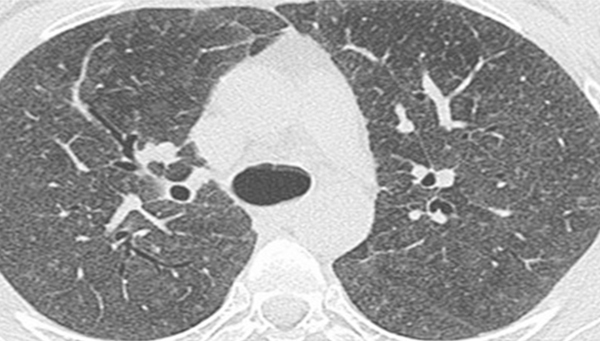

需要注意的是,「深肺癌前基因篩檢」的目的在於評估罹患肺癌的風險。即使檢測出來的分泌物中已存在致癌基因的主導型突變,雖然這些基因特徵與肺癌腫瘤細胞相似,但並不代表肺部已經出現傳統醫學定義上的癌組織或可診斷的腫瘤。傳統上,惡性腫瘤的定義包括細胞的失控生長、無限制的複製、對周圍組織的侵犯及遠距轉移。該檢測能夠確認肺部是否已出現與肺癌腫瘤組織相同的基因特徵,並結合臨床專家對LDCT(低劑量電腦斷層掃描)的判讀,幫助早期確診肺癌。

- 偵測<1/1000比例的基因突變,相當於0.01cm/1000萬顆突變細胞團塊/病灶比LDCT可見病灶(0.5cm/10E顆突變細胞病灶)偵測效果更佳

肺癌指的是肉眼可見病灶;LDGS偵測極微量的肺癌常見基因突變,並非真實看見腫瘤,但與罹患肺癌具有高度的相關性。